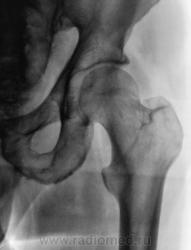

Травма 1 месяц тому. Пациент был направлен в рентгеновский кабинет для рентгенографии ребер и тазобедренного сустава. Был обнаружен перелом 2 - х ребер, но со стороны тазобедренного сустава нарушения целостности костной ткани и смещения костных отломков обнаружено не было.

Однако, пациент продолжал предъявлять жалобы на боли в области верхней трети бедра. Произведена рентгенография.

Тазобедренные суставы очень часто преподносят сюрпризы. Одним из них является вколоченный перелом шейки бедренной кости. За перелом в данном случае говорит:

1. Нескругленный угол между головкой и шейкой. Природа не любит острых (в смысле "нескругленных") углов.

2,Ненормальное расположение головки относительно шейки.

Все это потому, что произошло небольшое угловое смещение головки (или, правильнее, шейки), угол открыт кверху и латерально.

Укладка практически идеальная, а головка, если внимательно присмотреться, не на месте. А невидимость линии уплотнения - это тоже один из сюрпризов шейки бедра. Хотя, искать ее надо на первых снимках, да и то не всегда увидишь. Через месяц искать нужно тонкую полоску разряжения.